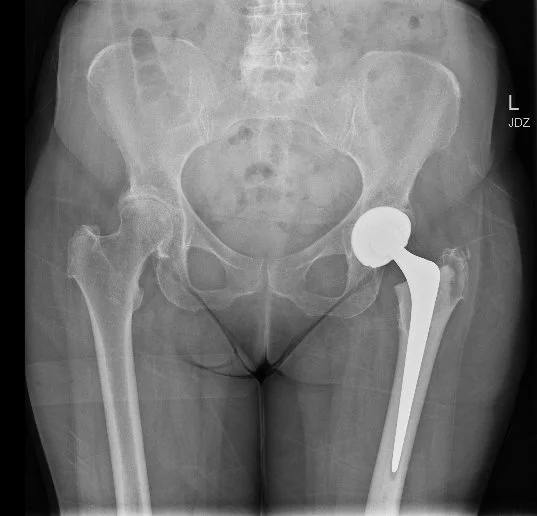

Hip Replacement

A hip replacement removes the worn surfaces of the hip joint and replaces them with smooth, durable artificial parts. The new ball and socket work together to reduce friction and improve movement.

It is considered when pain, stiffness, or loss of function from arthritis, avascular necrosis, or certain fractures limits daily life and non-surgical treatments are no longer effective.

The aims are to reduce pain, improve walking, and restore day-to-day comfort.

Modern implants have strong long-term results. About 90 to 95 percent function well at 15 years, with durability influenced by age, activity, and overall health.